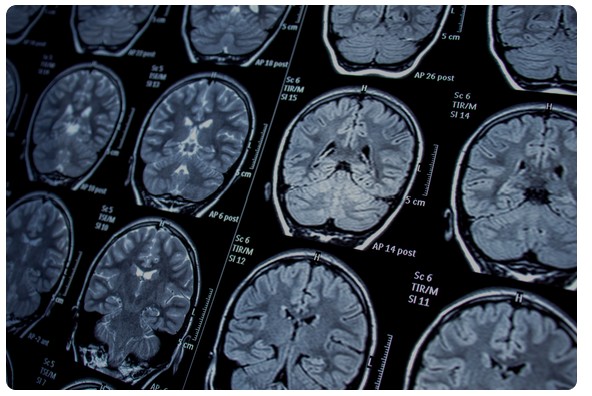

La plataforma de formación Campus CESM y la Fundación DEPFIM han informado de que se abre el plazo de inscripción para la primera edición del curso online Actualización en Neurología en Atención Primaria y Atención Hospitalaria, que contará con 3,9 créditos CTS.

El curso, impartido por Javier Martín, se desarrollará en 18 horas lectivas entre el 22 de septiembre y el 27 de octubre, y el objetivo es actualizar los conocimientos y habilidades clínicas de los profesionales sanitarios en el diagnóstico precoz, manejo terapéutico inicial y criterios de derivación de las principales urgencias neurológicas, con especial atención al ictus isquémico y hemorrágico, el protocolo Código Ictus y otras patologías neurológicas de alta prevalencia.